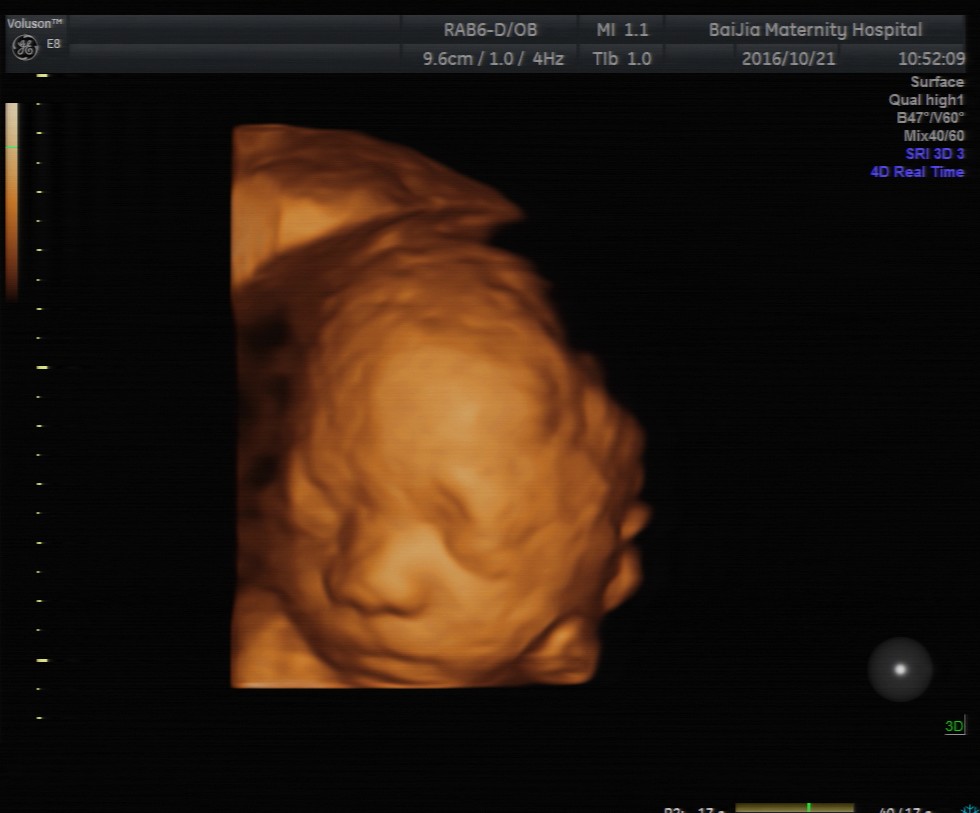

第一种:四维彩超是利用超声仪器中的软件将二维的平面图像模拟转换成动态、立体四维图像,有利于医生判断宝宝的发育情况是否正常以及是否存在重大畸形。检查时胎宝胎动比较频繁、表情动作也较多,像打哈欠、吸吮手指、吞咽口水等等,这些画面通过超声仪器呈现出来可能并不是那么好看。

第二种:胎宝宝的成长需要依附胎盘,所以面部可能紧贴着胎盘或者子宫壁引起变形,因此,在四维彩超成像时,宝宝的面部往往模糊不清,或某一部分直接变形,感觉比较丑。

第三种:四维彩超最佳检查时间段是孕20—24周,这个时期胎宝宝的各个器官刚刚发育完全,面部并不丰满,而四维彩超的成像是个放大的过程,所以可能出现大嘴、大鼻子、大脑门的外貌,看起来丑丑的。